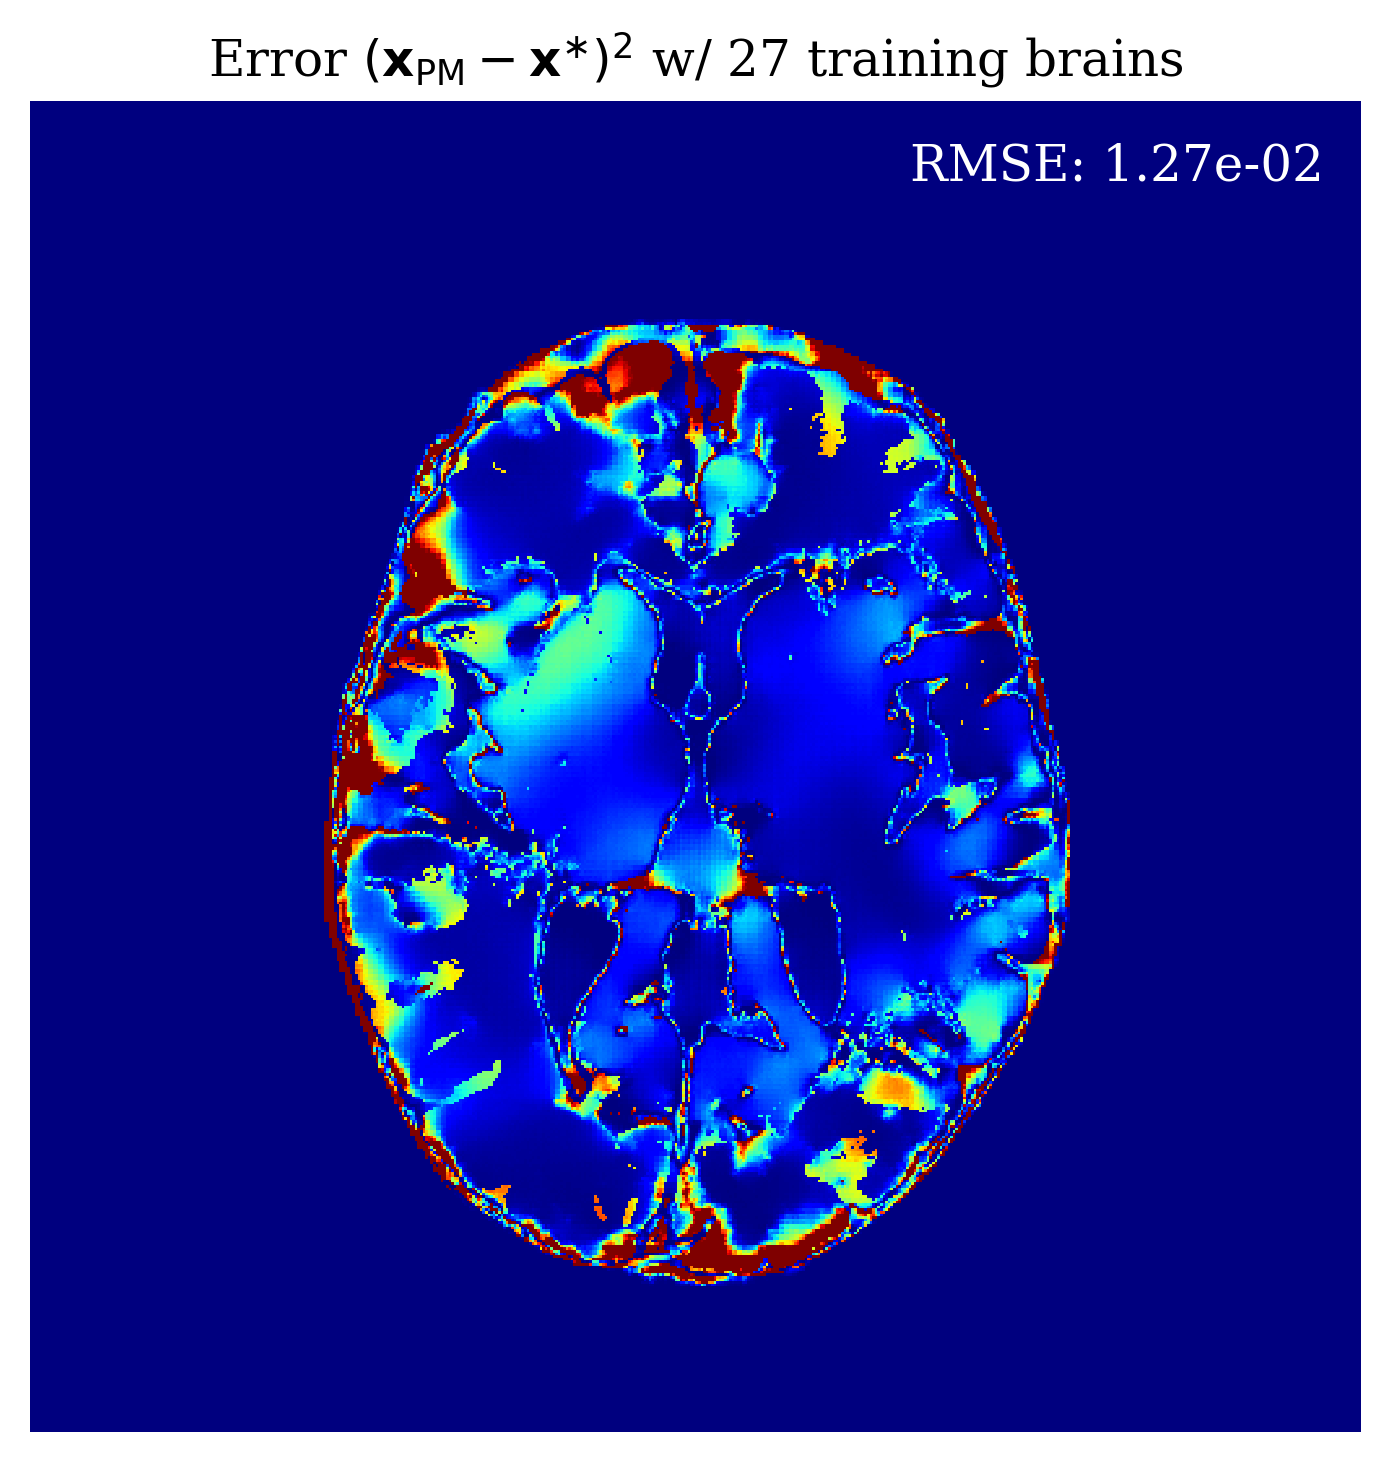

Since our method is Bayesian, its UQ results depend on how well it has learned the prior from training examples. In the case of conditional normalizing flows the prior is not explicitly accessible from the network since the network directly learns to sample the conditional distribution. Nonetheless, we would like to gain intuition on the effect of more training samples on the methods performance. In \figurereffig:trainingsize, we demonstrate the effect of increasing the training dataset size, on the posterior mean quality and on the UQ map that is produced. We observe from \figurereffig:trainingsize that as training samples increase, the posterior mean gets closer to the ground truth and that the UQ map becomes more contracted. These observations are similar to what happens when we increase the amount of observed data as explained in \sectionrefsec:uncertainty.

\subfigure

\subfigureUQ

\subfigureError

|

\subfigureGround truth